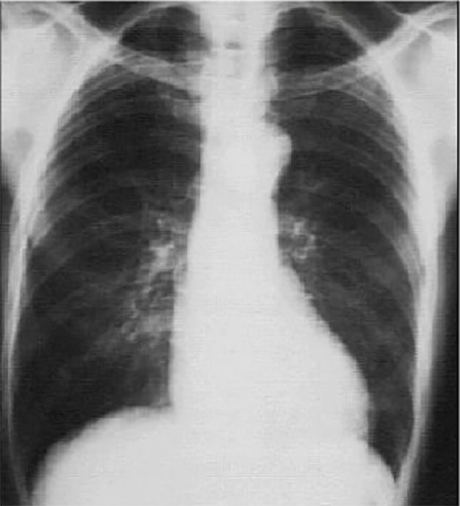

You are incorrect - the best interpretation of the chest X rays in our patient is that they are normal.

Your choice: Prominent aortic knob

This PA chest X ray shows an aortic knob that is prominent.

It is demonstrated by the greater than normal shadow created by the transverse aorta. Note that the cardiothoracic ratio is less than fifty percent, a normal finding. The pulmonary vasculature is normal. Although left ventricular mass may be increased, there is no evidence of ventricular dilatation.